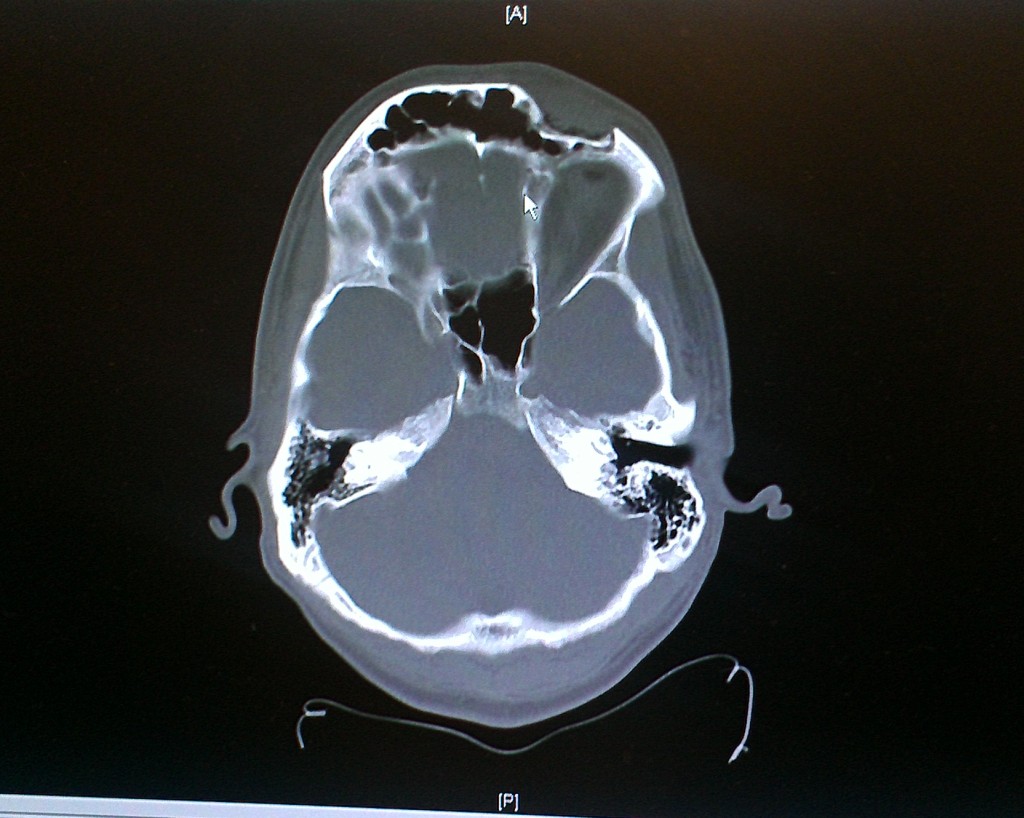

So Thursday night I was playing in the final softball game of the season, playing right field. Dude at the plate hits a hard tailing liner to right, I run up toward it and as I'm bringing my glove up, the ***** skips right across a bank of lights and I lose it completely. I move my glove up but the ball skips right across the top and nails me just above the left eye.

A few hours later after an ER trip, I've got a broken frontal orbital bone, a few stitches above the eye, and a ton of swelling. I'll be going to an ENT on Wednesday to be checked out because the orbit fractured in a few places and is displaced back into the sinus.

So, met with the ENT surgeon this morning. Surgery is a definite, no question about it. The big question right now is whether they will be able to go in through the small laceration just below my eyebrow (thus minimizing additional scarring) or have to cut my scalp across the top and pull my forehead down over my face (oh! what a great Halloween costume that would have made). Looking like it'll be scheduled for the end of next week, as waiting any longer than 2 weeks will allow the bones to heal too much.